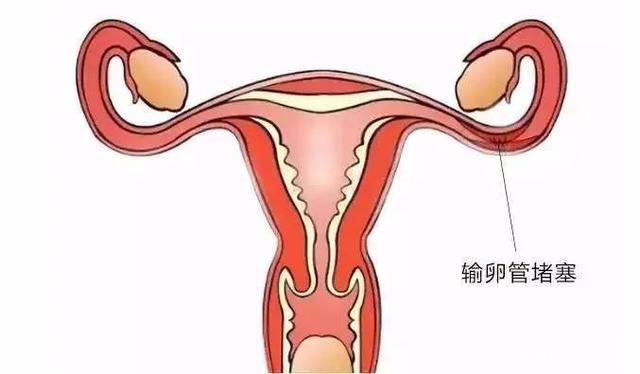

盆腔炎,是女性生殖道炎症及其周围组织的炎症,主要有子宫内膜炎、输卵管炎、输卵管卵巢脓肿、盆腔腹膜炎。炎症可感染一个部位,也会互相感染后几个部位都感染。盆腔炎的症状主要表现为白带增多、下腹坠胀疼痛、腰骰疼痛、或肛门坠胀、痛经、月经不调、不孕症、或伴有尿频。

盆腔炎最大的危害是造成不孕症。妇女盆腔内子宫、输卵管及卵巢或其周围的组织,包括盆腔内腹膜,任何一处发生炎症时,都可以造成妇女不孕。当急性炎症未能彻底治疗时转变成慢性,或者盆腔炎治疗不及时,迁延成慢性时,常常造成妇女不孕。盆腔炎引起的不孕症西医手段很难治疗,有些使用手术治疗的患者即便用手术治疗成功,也会因为炎症未能清除而无法根除症状。